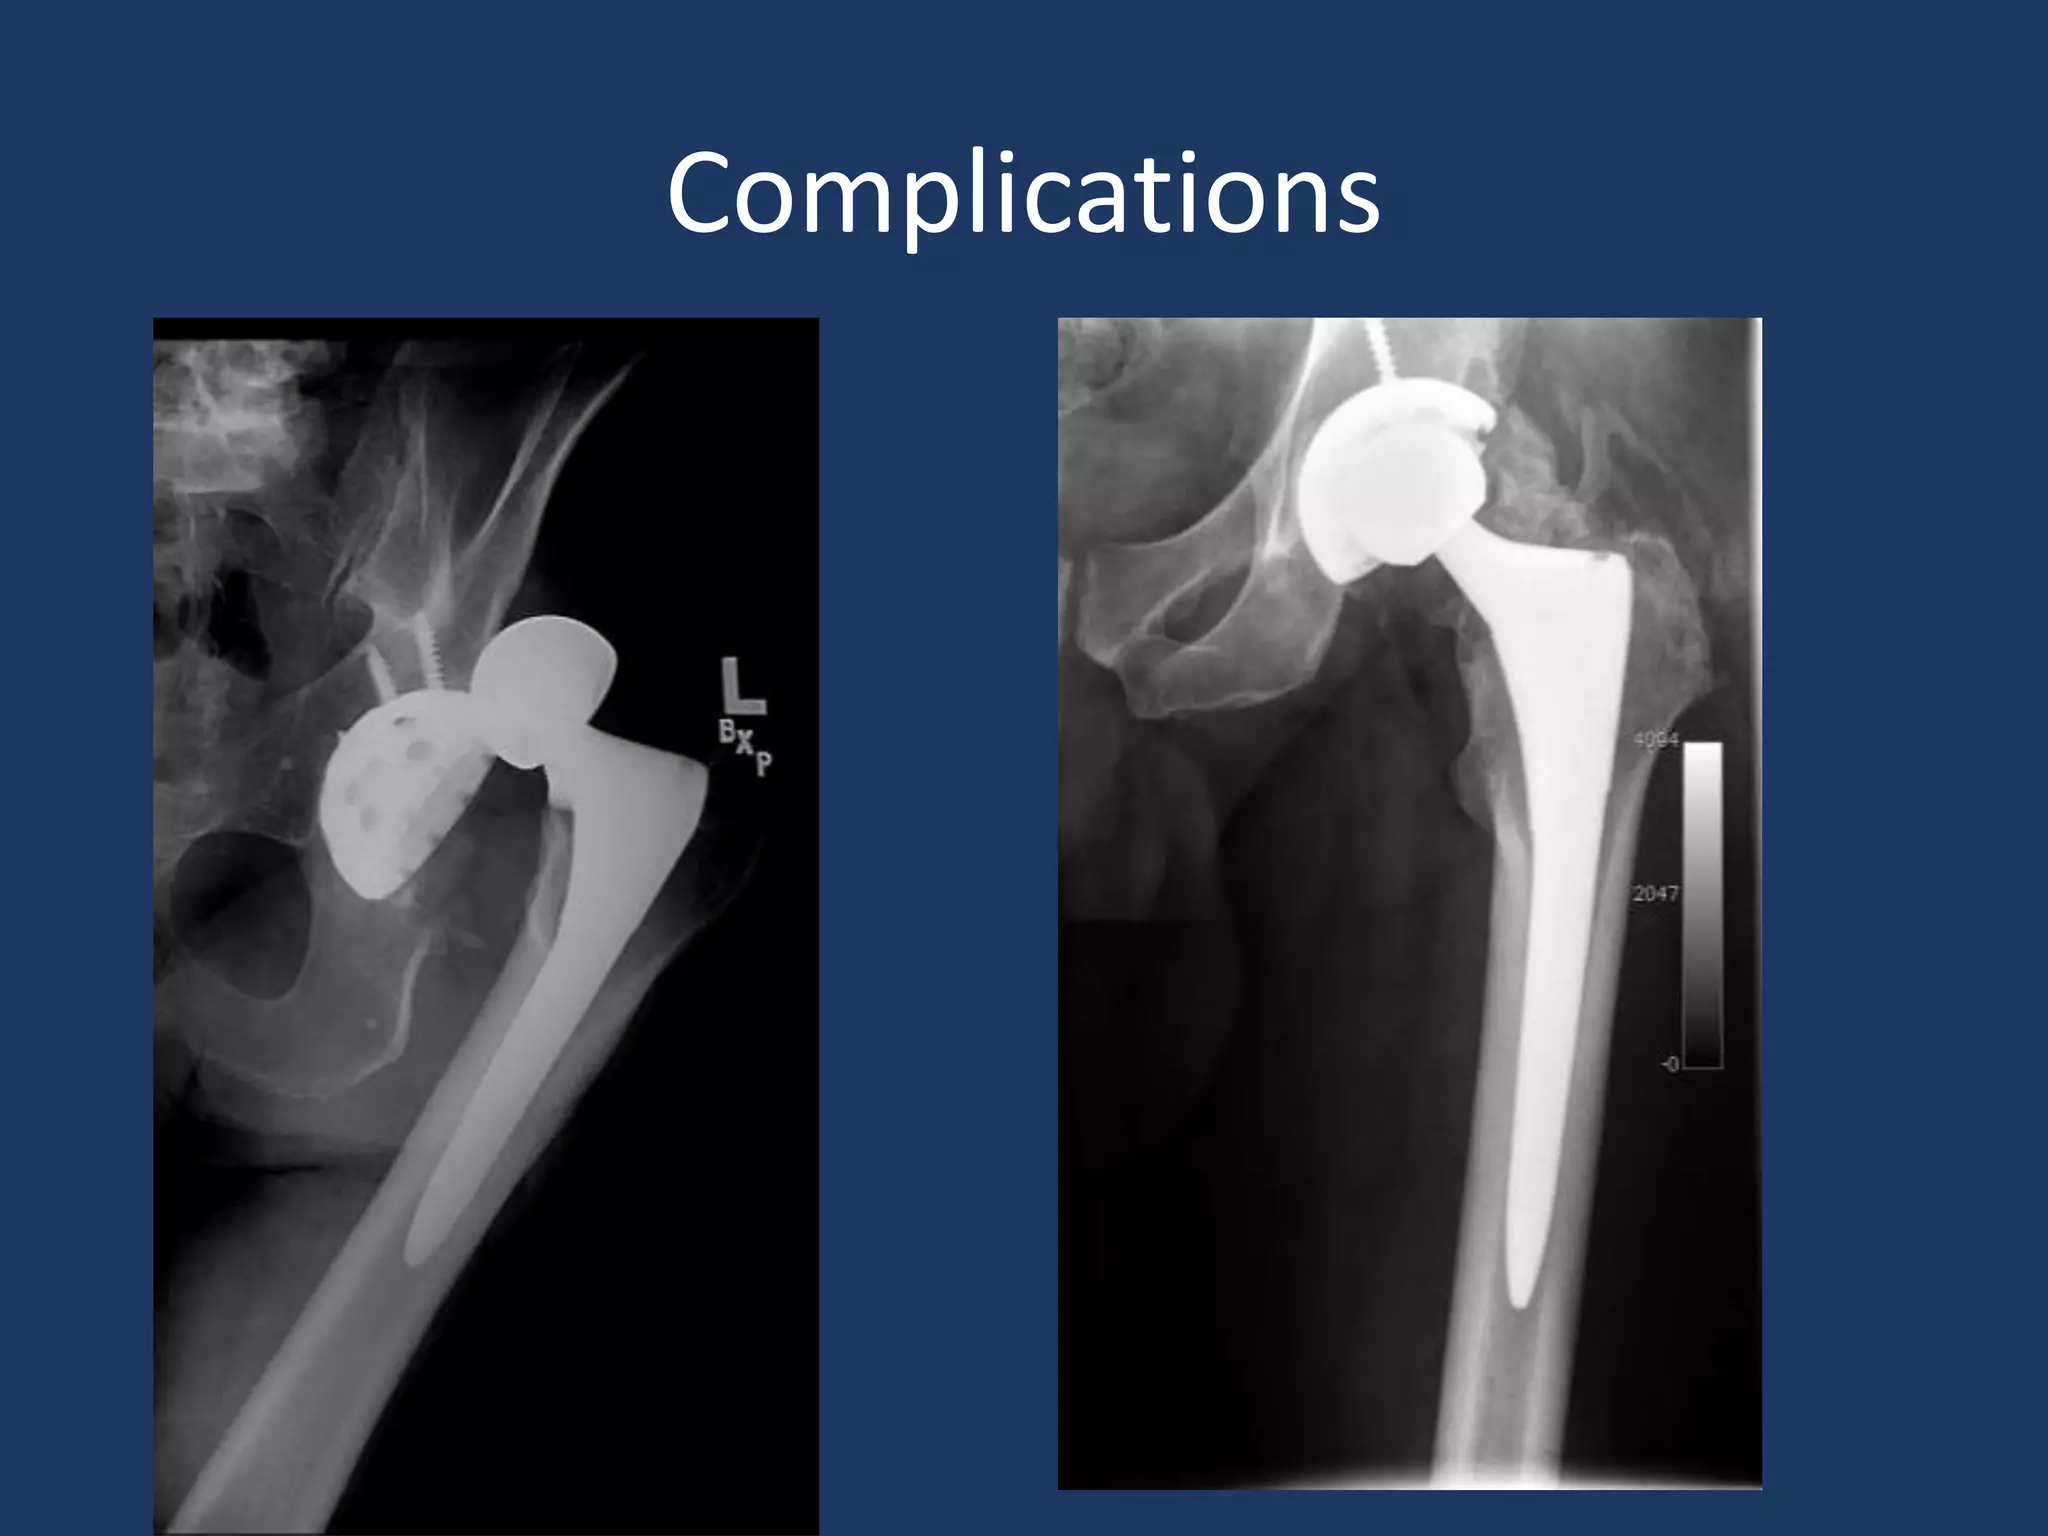

Complications

• Most of these studies demonstrated minor

short term recovery improvements, with no

difference to standard approach at 3 months.

• Complications rates were generally higher

– Blood loss

– Component malposition

– Soft tissue injury